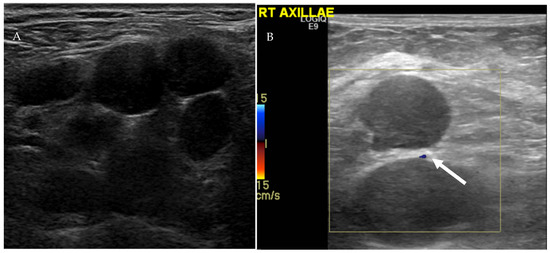

. You suspect a dentalperiodontal infection. The US examination for axillary pain demonstrated lymph node with abnormal cortical thickening of 6 mm Fig 5 B. The most common lumps or swellings are enlarged lymph nodes.

Idiopathic multicentric Castleman disease iMCD is a subtype of Castleman disease also known as giant lymph node hyperplasia lymphoid hamartoma or angiofollicular lymph node hyperplasia a group of lymphoproliferative disorders characterized by lymph node enlargement characteristic features on microscopic analysis of enlarged lymph node tissue and a range of. There were abnormal right axillary lymph nodes with increased eccentric hypoechoic cortical thickening measuring up to 5 mm above the normal value of 23 mm used at our institution Royal Free London NHS Trust Figure 3b.